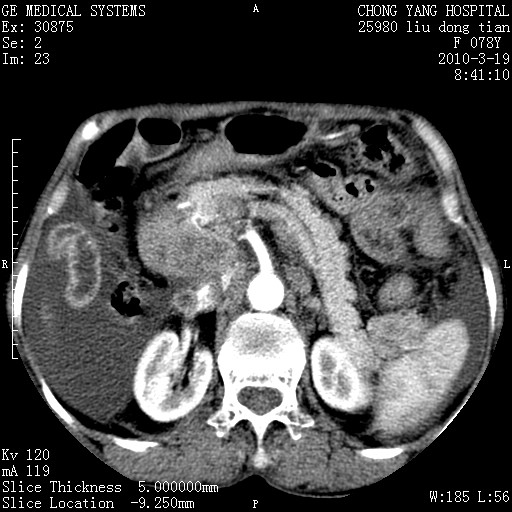

标题: CT25199:F 78Y 腹胀半年 消瘦乏力 [打印本页]

胆囊壁增厚并明显强化,胆囊癌伴多发转移瘤可能性大,淋巴瘤不除外,右肾囊肿,胸腹水.

考虑nhl,肝、脾、腹膜腔及腹膜后多发淋巴结受侵,腹水,右肾囊肿,慢性胆囊炎,右侧少量胸腔积液。

胰头有肿块形成,胰头ca伴肝脾、腹膜腹膜后转移

胆囊有软组织影有强化,支持胆囊癌,肝脾、腹膜后淋巴结转移。

nhl的淋巴结多围绕主动脉,而且主动脉会移位,所以不考虑nhl。

分开来讲:肝左叶、尾叶病灶有不均强化像肝癌;

脾脏病灶无强化,像多发囊肿或淋巴管瘤,不除外淋巴瘤(低强化);

胆囊增生性病变:胆囊癌,腺肌增生症,慢性胆囊炎;

肝门、胰腺头、腹膜后多个团块: 淋巴瘤,转移;

腔静脉肝内段细小有无布加可能?

一元论最好了 淋巴瘤所致改变; 胆囊癌转移不像,胆囊周围肝组织清晰,肝癌淋巴结转移?三元论都不止。

最后报的胰头癌多发转移,脾脏单独考虑囊肿或淋巴管瘤。